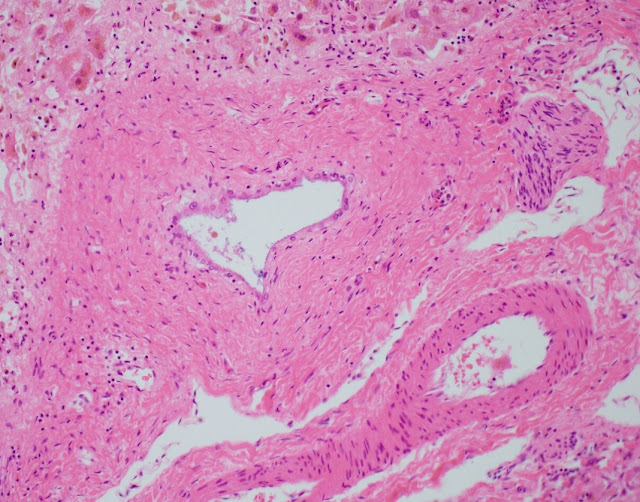

The explant showed submassive hepatocellular necrosis with marked cholestasis, and markedly dystrophic changes in bile duct epithelium in the portal tracts, but there was no ductopenia. Ductular reaction was conspicuously absent. The portal tracts showed mild chronic inflammatory infiltrate, associated with mild focal endothelialitis, and reduced number of small arterial branches. Medium-sized bile ducts showed periductal fibrosis along with dystrophic epithelial changes. Large bile ducts showed foci of intraepithelial lymphocytes, and focal reactive changes. There was central perivenulitis, with foci of lobular microabscesses. There was no foam cell arterial lesion, fibro-muscular intimal thickening, or inflammatory infiltration of muscular arteries. Trichrome stain highlighted fine perisinusoidal fibrosis, extending to portal tracts, but there is no bridging fibrosis. Reticulin showed a largely preserved architecture. A cytomegalovirus immunostain was negative.

Histologic features of chronic rejection and ischemia.